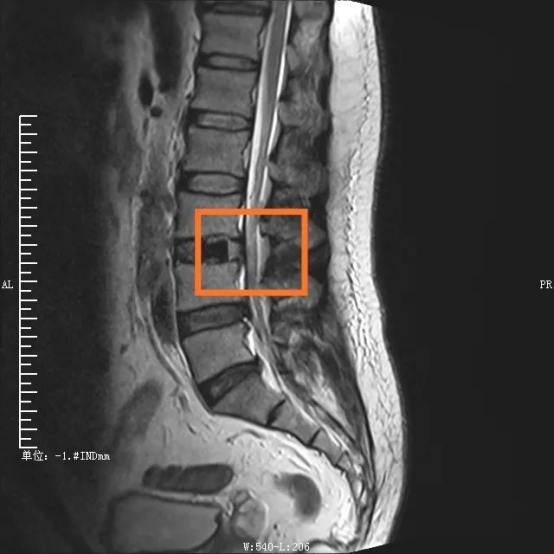

手術(shù)部位術(shù)前/術(shù)后對比圖

在外科醫(yī)生眼中,衡量一臺手術(shù)是否成功、是否屬于微創(chuàng)范疇,術(shù)中的出血量、組織損傷、手術(shù)時間以及術(shù)后康復(fù)時間都是重要考量因素。傳統(tǒng)腰椎手術(shù)從后方入路,需要切開分離肌肉組織,手術(shù)創(chuàng)傷大,時間長,出血量多??紤]到傳統(tǒng)手術(shù)對患者肌肉等組織損傷較大,且手術(shù)費用及住院時間增加,脊柱脊髓專業(yè)組決定采取更安全高效的OLIF手術(shù)。

“OLIF手術(shù)采用側(cè)方入路,手術(shù)區(qū)域在椎管前方,不破壞后方結(jié)構(gòu),不分離脊柱后方肌肉,極大地減少了組織損傷?!编?yán)捉榻B,這種技術(shù)巧妙在于,充分了利用腹膜后主動脈與腰大肌前緣之間的自然間隙,到達目標(biāo)椎體斜外側(cè),結(jié)合神經(jīng)外科顯微手術(shù)技術(shù),切除病變椎間盤,實現(xiàn)椎間融合。若手術(shù)順利,術(shù)中患者出血僅20ml左右,患者術(shù)后2天就能下床活動,3天即可出院。